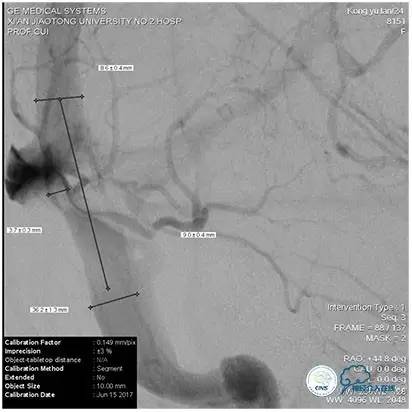

术中造影

5ml/s,总量8ml,压力100~150

1、6mm×20mmAviator球囊(Cordis)分段对狭窄部位进行扩张。

2、植入7mm×40mmPrecise自膨支架。

2、术中再次测量血管直径,选择恰当球囊缓慢扩张,避免过度扩张,造成静脉窦与颅骨剥离形成硬膜外血肿;

3、球囊扩张状态下行同侧颈内动脉或椎动脉造影,了解穿支静脉回流状况,如穿支回流缓慢,则选择比静脉窦测量直径小1~2mm的支架;术后发生皮层静脉回流受阻所导致的的梗死、出血风险要小。